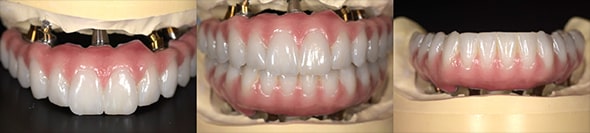

オールオン4+α(All-on-4+α)とは、上下に最少4本ずつのインプラントを埋入し、総入れ歯の形をした上部構造を固定して短時間で見た目と噛み合わせ機能を回復させる治療法です。

とびきり美しい上部構造

ただ治すのではなく、美しく治す。しかも、とびっきり美しく治すことにこだわっています。そのため、数々の賞を受賞する腕の良い歯科技工士と連携して歯をデザインしています。